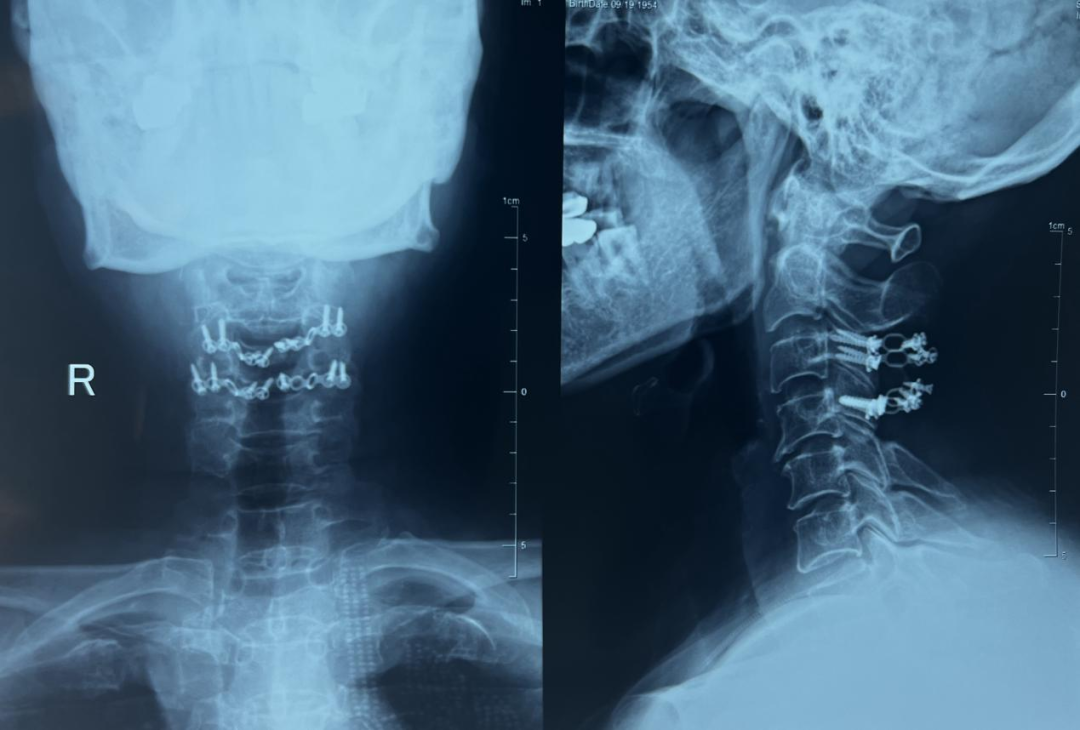

一年来,患者按时随访,没有出现任何异常。术后一年查体显示患者可以正常前屈后伸,颈椎活动度正常,复查影像资料显示,肿瘤完全切除,脊髓减压彻底,内固定良好,脊柱稳定性无异常。

内固定在位、脊柱稳定性良好